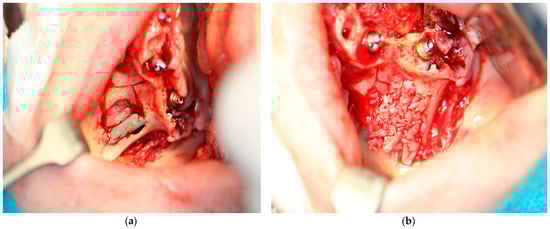

2.5.1. Subperiosteal Implants

Surgical Technique